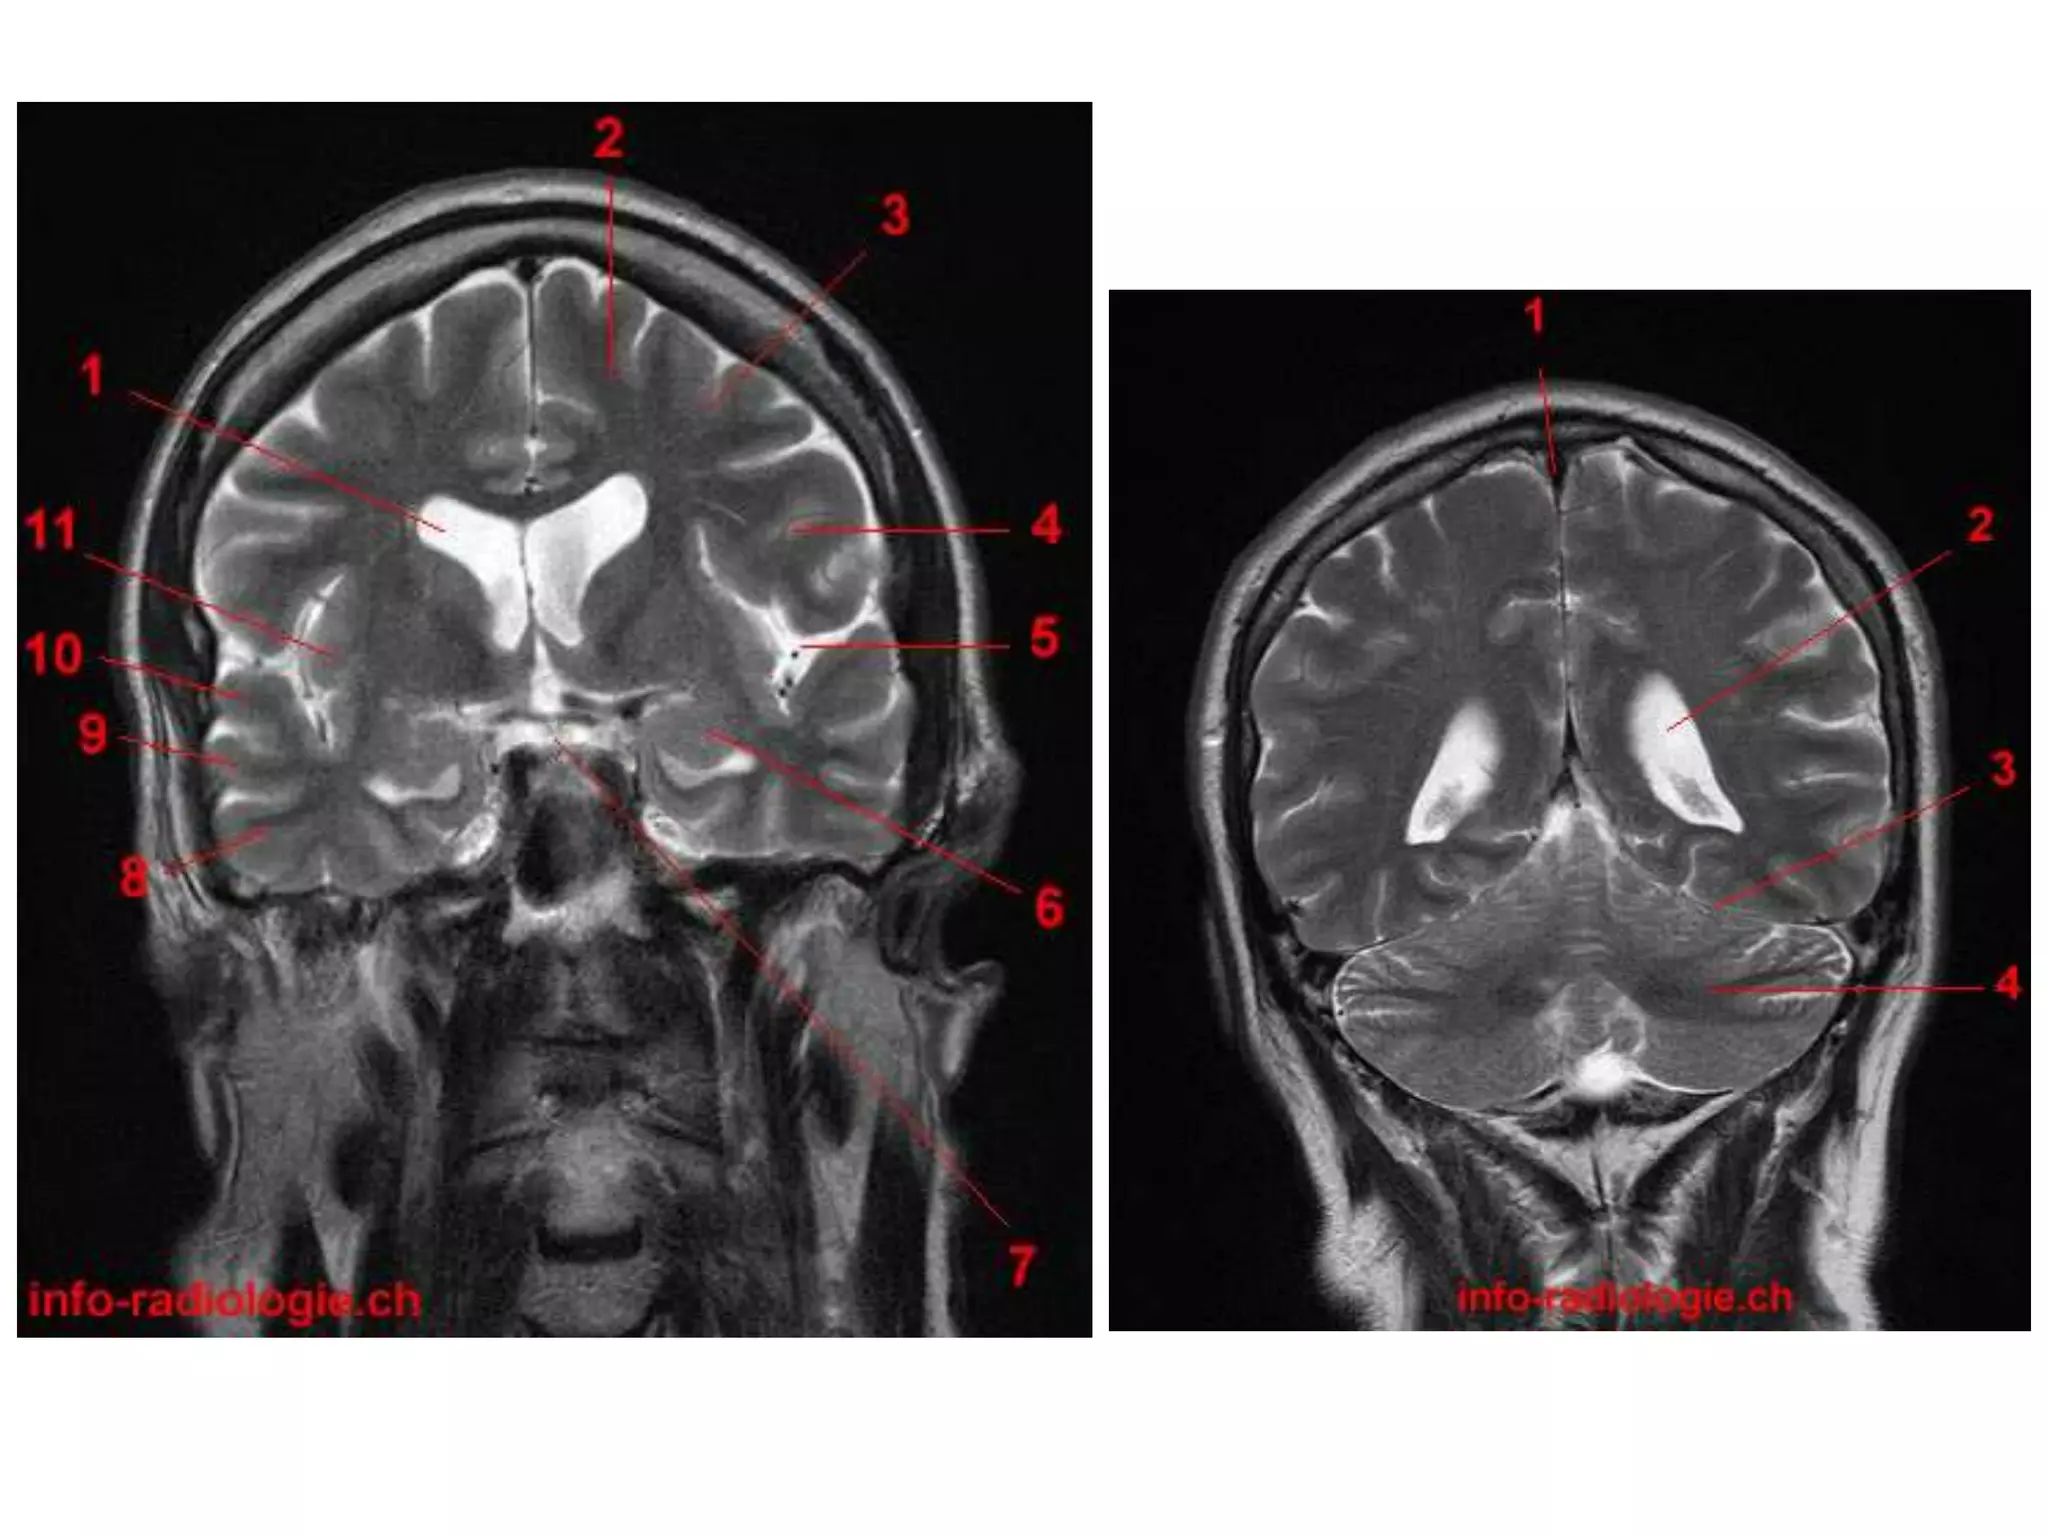

Coronal : frontal horns – inverted triangle

body – flattened

temporal horns – like ‘C’ on its sides.

Lateral ventricle • Parts: Horns – Frontal, Occipital and Temporal. Body Trigone / Atrium • Relations : supr. – C. callosum infr. – choroid plexus, thalamus and hippocampus lat – caudate nucleus med – S. pellucidum and fornix

• 73.

Septum pellucidum :seperates lateral ventricles (FH and body). • It is a midline triangular sheet attached above to C.callosum and postr.ly to fornix. • It has 2 laminae with narrow cavity. ( cavum SP – due to seperation of 2 laminae. In 10% adults )

• 74.

• Radiology – Axial MRI / CT : frontal horns separated by S. pellucidum and posteriorly lateral ventricles diverge and pass into temporal and occipital horns. Saggital MRI : ‘C’ shaped , curving round the thalamus.

• 76.

• Radiology – Axial MRI / CT : frontal horns separated by S. pellucidum and posteriorly lateral ventricles diverge and pass into temporal and occipital horns. Saggital MRI : ‘C’ shaped , curving round the thalamus. Coronal : frontal horns – inverted triangle body – flattened temporal horns – like ‘C’ on its sides.